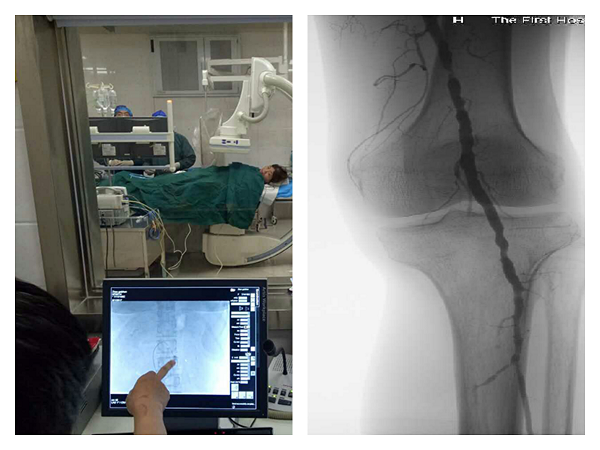

(1)糖尿病:①糖尿病足的三级预防及管理;②糖尿病足的管理及足部感染细菌谱的研究;③糖尿病慢性病信息化管理。以健康教育为主体,在药物治疗的基础上开展糖尿病足局部伤口换药、介入治疗及手术治疗,同时开展糖尿病及其相关并发症基础与临床的前沿研究;同时进行糖尿病慢性病信息化管理。